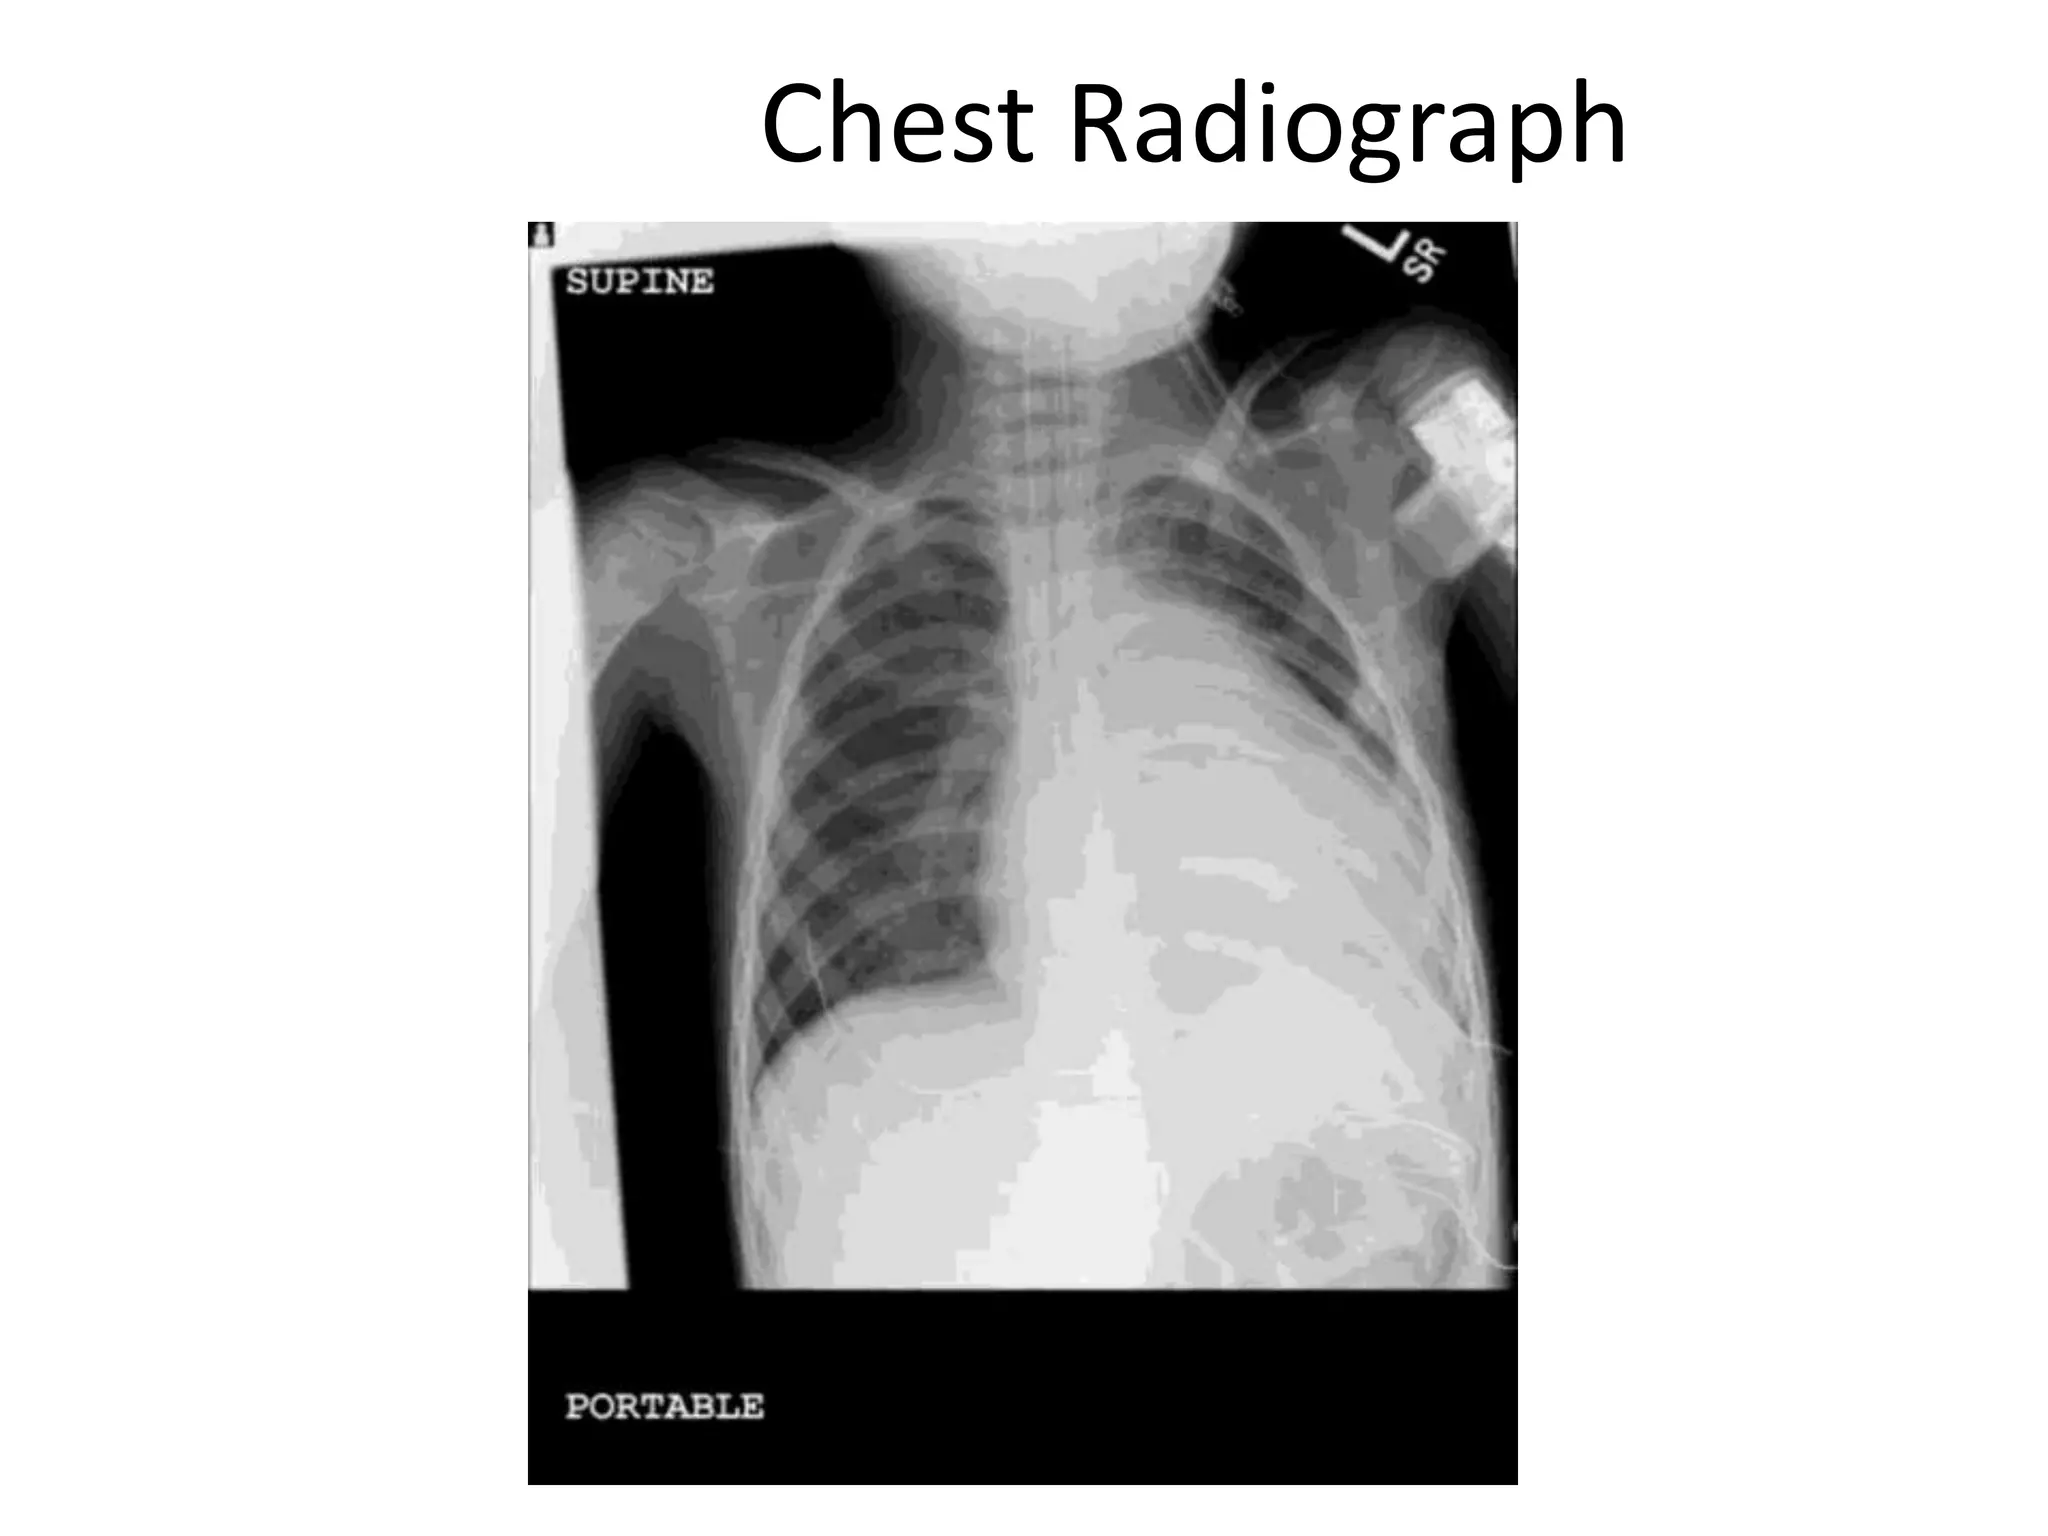

• Chest X-Ray- Variable (Normal to Cardiomegaly)

Chest Radiograph